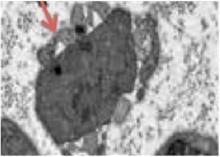

La autofagia de las células de Schwann durante la degeneración walleriana o mielinofagia implica la formación de una doble membrana de aislamiento intracelular que envuelve una determinada carga citoplasmática y la transfiere a los lisosomas para su degradación, denominada autofagosoma y está dirigida a destruir la mielina contenida en el interior de las células de Schwann. De esta manera, la vaina de mielina es fragmentada en segmentos ovalados y su degeneración continúa hasta ser reducida a detritus intracelulares, proceso que ocurre durante los primeros cinco o siete días después de la lesión. La segunda fase de desmielinización ocurre por fagocitosis, que es un proceso extrínseco, al atraer macrófagos hematógenos hacia el nervio lesionado por parte de las células de Schwann, y estos, con ayuda de anticuerpos y el complemento, se encargan de la mayor parte de la degeneración de los lípidos y proteínas mielínicas. Las células de Schwann también pueden intervenir en esta fase ayudando a fagocitar los detritus de mielina restantes [2].